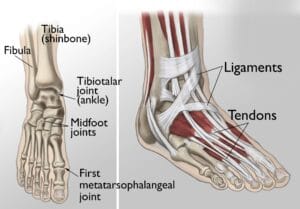

Anatomy

(Left) The joints of the ankle, midfoot, and big toe are commonly affected by arthritis. (Right) Ligaments and tendons connect the bones to each other and to the surrounding muscles of the lower leg.Reproduced and modified from The Body Almanac. © American Academy of Orthopaedic Surgeons, 2003.